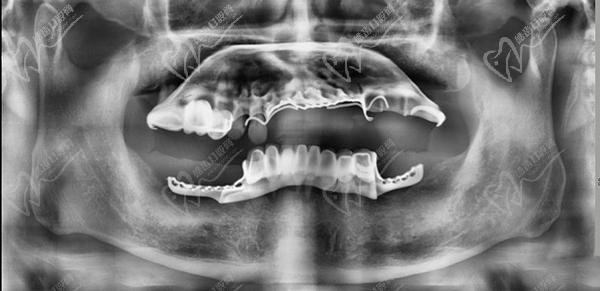

1、術(shù)前檢查和評估:進(jìn)行X光片、CT等影像學(xué)檢查,以確定患者的牙槽骨質(zhì)量和數(shù)量,為手術(shù)方案的指定提供數(shù)據(jù)支持。一般家里的老人患有基礎(chǔ)疾病的只要身體健康、口腔條件達(dá)標(biāo)都可以做,對全口牙齒重度松動的中青年患者亟需修復(fù)的可以做。

重度牙周炎會導(dǎo)致牙齒松動、脫落和牙槽骨的破壞。全口即拔即種種植牙適用于牙周炎患者,可以在一次手術(shù)中同時(shí)拔除松動的牙齒并植入種植體。在手術(shù)前,需要進(jìn)行詳細(xì)的口腔檢查和評估,包括X光片、CT等影像學(xué)檢查,以確定患者的牙槽骨質(zhì)量和數(shù)量。在手術(shù)中,局部麻醉后拔除松動的牙齒,然后在拔牙后的創(chuàng)口內(nèi)植入種植體,并進(jìn)行縫合。術(shù)后需要指導(dǎo)患者進(jìn)行日常護(hù)理和藥物治療,確保創(chuàng)口愈合良好。